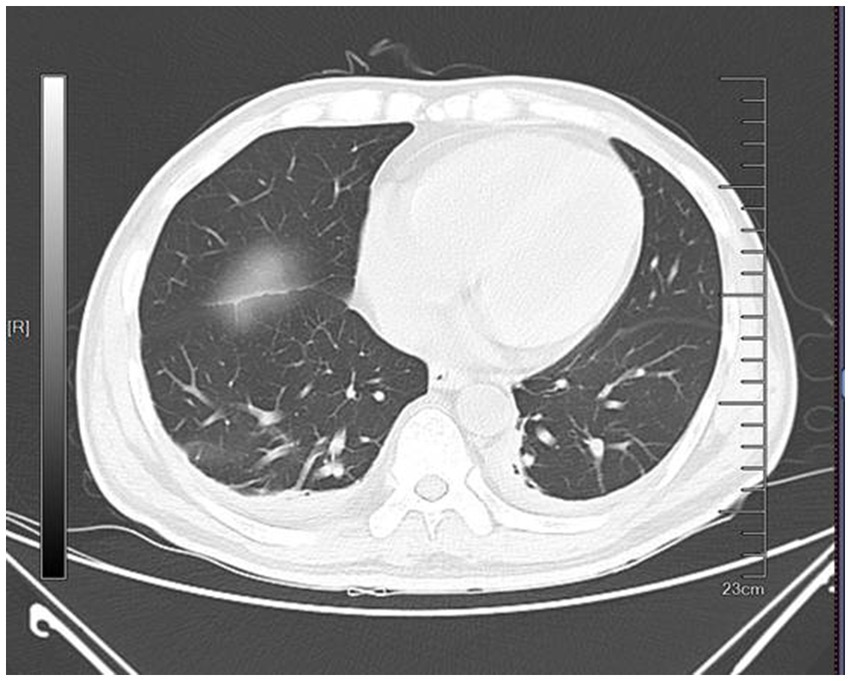

Physical examination revealed pallor of the conjunctivae and palmar creases, tachycardia (heart rate: 112 bpm), and active epistaxis. No icteric sclera, splenomegaly, or petechiae were observed. Complete blood count revealed leukocyte counts of 5.94 × 109/L [normal (3.5–9.5) × 109/L], severe anemia with a hemoglobin level of 61.0 g/L [normal 130–175 g/L], and a platelet count of 345 × 109/L [normal (125–350) × 109/L]. The erythrocyte indices showed macrocytosis (MCV 111.9 fL) and a decreased mean corpuscular hemoglobin concentration (MCHC 295 g/L). Peripheral blood smear examination revealed: marked RBC agglutination at room temperature, spherocytes (approximately 15% of RBCs), absence of schistocytes, microspherocytes, or bite cells, polychromasia (indicating reticulocytosis), and leukocyte and platelet morphology within normal limits. A direct antiglobulin test (DAT) was positive, notably for complement C3d, which is characteristic of CAD. The aPTT was significantly prolonged at 88.60 s. Biochemical markers of hemolysis were elevated: total bilirubin was 43.9 μmol/L (with an indirect bilirubin predominance of 29.00 μmol/L), and lactate dehydrogenase was 274 U/L. Coagulation studies confirmed the diagnosis of AHA, with a factor VIII activity level of 1.4% and a factor VIII inhibitor titer of 3.6 Bethesda units (BU). Serological testing demonstrated a high cold agglutinin titer of 1:320, which is diagnostic for CAD. G6PD activity was normal at 12.5 U/g Hb (reference: 7.0–20.5 U/g Hb). ADAMTS13 activity was 78% (reference: ≥67%). The immunofixation was negative. A comprehensive evaluation was undertaken to identify underlying triggers. Serological tests for common autoimmune connective tissue diseases (e.g., antinuclear antibodies, rheumatoid factor) were negative. No evidence of solid malignancy was found on contrast-enhanced CT imaging of the chest, abdomen, and pelvis, or on endoscopic evaluation. Serum protein electrophoresis and immunofixation showed no monoclonal gammopathy, excluding a plasma cell dyscrasia. Serologies for acute hepatitis (A, B, C), HIV, and Epstein–Barr virus were likewise negative. Thus, this case was classified as idiopathic. Diagnostic evaluation of AHA adhered to standardized protocols: blood smear excluded microangiopathic hemolysis, DIC was objectively ruled out by ISTH criteria using serial coagulation profiles, G6PD/PNH testing and ADAMTS13 activity confirmed alternative etiologies were unlikely. The diagnosis of CAD was confirmed based on the presence of chronic hemolytic anemia, characteristic cold-induced acrocyanosis and hemoglobinuria, a positive DAT, and a significantly elevated cold agglutinin titer of 1:320, which is well above the diagnostic threshold of 1:64 at 4 °C, in the absence of underlying lymphoproliferative disorders, infections, or other secondary causes. Concurrently, the diagnosis of AHA was established by the presence of spontaneous bleeding episodes (including epistaxis and historical gastrointestinal bleeding), markedly prolonged activated partial thromboplastin time (aPTT), severely reduced factor VIII activity (1.4%), and the detection of a factor VIII inhibitor at 3.6 Bethesda units, confirming an autoimmune etiology for the coagulopathy. Thus, based on the patient’s clinical manifestations and laboratory findings, a definitive diagnosis of concurrent CAD and AHA was established. The co-occurrence of these two rare autoimmune disorders suggests a shared underlying immune pathophysiology, potentially involving epitope spreading in a genetically susceptible individual. Initial immunosuppressive therapy consisted of corticosteroids (prednisone 1 mg/kg/day) and cyclophosphamide (100 mg/day). However, consistent with literature indicating poor response to steroids in CAD (2, 3), the patient showed minimal improvement. Pulse therapy with methylprednisolone (200 mg daily for 4 days) was subsequently administered, followed by a gradual taper. In addition, prothrombin complex concentrate (PCC) and packed red blood cells (PRBCs) were transfused to improve coagulation function and correct anemia, respectively. During the corticosteroid taper, the patient developed hospital-acquired pneumonia (Figure 1), which progressed to septic shock—a known risk associated with intensive immunosuppression. Concurrently, laboratory parameters worsened, with recurrent prolongation of aPTT and declining hemoglobin levels. Given the inadequate response to initial therapy and the complications encountered, treatment with rituximab (375 mg/m2 weekly for 4 weeks) was initiated, reflecting a targeted B-cell depletion strategy supported by evidence in both CAD and AHA (2, 7). Following rituximab administration, the patient’s aPTT normalized, indicating a promising biochemical response. The dynamic changes in hemoglobin and aPTT throughout the clinical course are illustrated in Figures 2, 3.

Figure 1. CT image of the patient’s chest. The CT showed bilateral pulmonary exudative changes and bilateral pleural effusion.